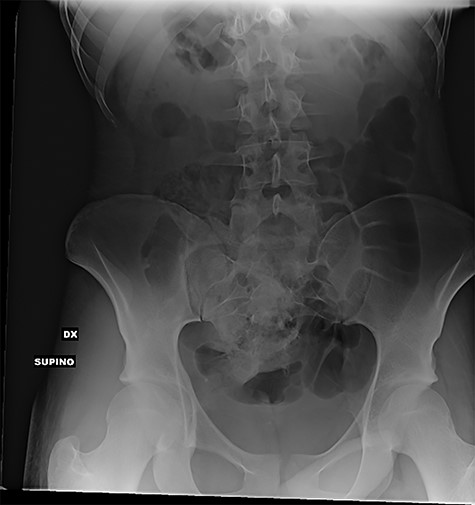

At hospitalization, the clinical examination revealed moderate pain in the lower left part of the abdomen. Laboratory analyses demonstrated moderate neutrophilic leukocytosis. Abdominal X-rays revealed the presence of many radiopaque foreign bodies on the projection of the rectum, referable to stylus batteries (Figs 1 and 2).

Erect abdominal X-rays (lateral view): confirmation of the presence of many radiopaque foreign bodies in the pelvis